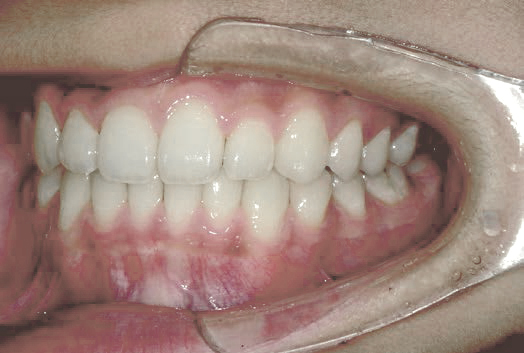

出っ歯

あごや骨格を正しく成長させる矯正治療

Aさん (矯正開始時:8歳)

Before

After

鼻がつまりやすく、口呼吸をしているために上あごが狭い状態でした。また上の前歯がかなり前へ傾いているため、お口をきちんと閉じていることができません。さらに、下の前歯もでこぼこしていました。

治療を終えて

装置によって上あごを拡大し、下あごを少し前へ成長させたことで、永久歯がきれいに並ぶスペースを確保しました。また、お口の機能が向上したことから鼻がよく通るようになり、口呼吸も改善され口も閉じやすくなったので顔の表情もよくなりました。

主訴・治療内容 下あごが後ろに下がり、出っ歯のようになっていることを心配して、無料相談に来院されました。

治療期間 2年半

費用 462,000円(税込)